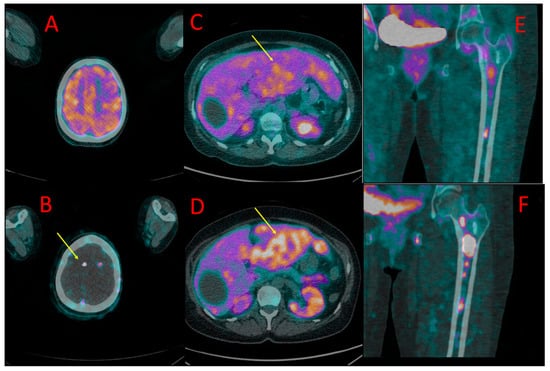

Figure 3. One of the brain metastases in patient #4 detected in [18F]PSMA-1007 (B) but not in [18F]FDG PET/CT (A). Diffuse liver metastases showed higher uptake of [18F]PSMA-1007 (D) than of [18F]FDG (C). More bone metastases in the left femoral bone were detected, and higher radiotracer accumulation in these lesions was found in 18F-PSMA PET/CT (F) in comparison to [18F]FDG (E).

Liver metastases (up to 67 mm) showed higher [18F]PSMA-1007 uptake than [18F]FDG (SUVmax = 17.3 vs. 4.1, TBR 3.4 vs. 1.8) (Figure 3C,D).

Metastases in both adrenals (20 and 55 mm) also presented with higher [18F]PSMA-1007 accumulation than 18F-FDG (SUVmax = 11.7 vs. 2.3, TBR 2, 3 vs. 1.7).

Approximately ten small brain metastases (diameter ranging from 4 to 7 mm) were detected only with the use of [18F]PSMA-1007 PET/CT (they were [18F]FDG-negative) (Figure 3A,B). The central nervous system metastases were subsequently confirmed using brain MR.